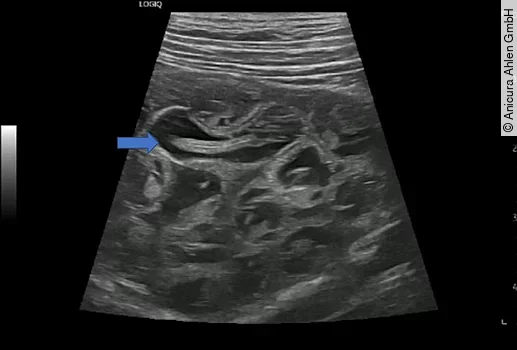

Eine weitere Methode zum Nachweis von Dioctophyma renale ist die Bildgebung. In der Röntgenuntersuchung kann unspezifisch eine Renomegalie der rechten Niere auffallen [11]. Die Sonographie ist spezifischer oder sogar, wie im hier vorliegenden Praxisfall diagnostisch (Abb. 7 und 8). Die rechte Niere stellt sich insgesamt vergrößert und durch sichtbaren Wurmbefall deformiert dar. Das Nierenparenchym verliert durch zunehmende Druckatrophie seine normale Architektur und wird ersetzt durch den/die wachsenden Parasiten und entzündliches Exsudat. Dies stellt sich sonographisch als multiple anechogene Rundherde mit hyperechogener Kapsel und darin doppellineare, tubuläre, mobile Strukturen dar [4,11,12,13].

Ein drei Jahre alter männlich-kastrierter Mischlingsrüde wird aufgrund einer Dysurie vorgestellt. Der Hund stammt ursprünglich aus Kasachstan und wurde über Russland nach Deutschland eingeführt. Die klinische Untersuchung verläuft unauffällig, doch können mittels Urinuntersuchung sowohl Eier von Capillaria plica als auch Dioctophyma renale nachgewiesen werden. Während die Capillariainfektion medikamentös mit Fenbendazol behandelt wird, erfolgt aufgrund der Dioctophymiasis eine abdominale Sonographie und identifiziert einen Wurmbefall der rechten Niere (Abb. 3). Nachdem eine Blutuntersuchung eine unauffällige Nierenfunktion zeigt, folgt die unilaterale Nephrektomie. Der Patient übersteht den Eingriff komplikationslos und wird einen Tag post operationem in die haustierärztliche Nachsorge entlassen.